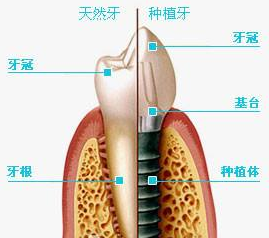

种植牙是一种利用生物材料,通过高科技手段修复缺牙的治疗技术。种值牙就是将人工材料制成的种植体(即“人工牙根”)植入缺牙区的牙槽骨内,上部的基桩暴露在口腔内,再在基桩上接上烤瓷牙。种植牙的手术很小,无需住院,手术完全无痛,术后即可进食。种植术后3-6个月待种植牙牙根与颌骨形成骨性结合后,即可在种植牙根上制作假牙。治疗过程中可以戴用暂时性的假牙。种植手术的最佳时机是拔牙后2月至1年。